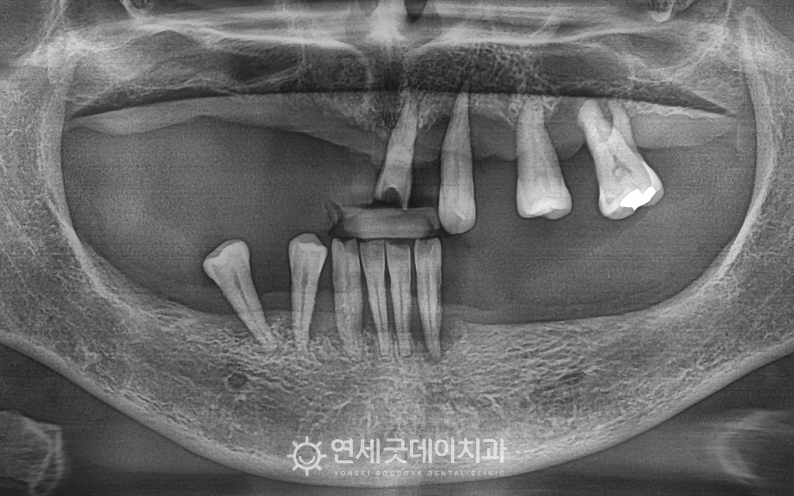

전체임플란트 및 상악동수술 치료전후 (50대)

환자분은 앞니와 일부 치아만 보이고

엑스레이 상에서도 여러 치아가 이미 빠져있었으며 잇몸뼈 역시 치아 상실 후 뼈흡수로 인해 무엇보다 어금니 부위 대부분이 상실되어 있어

남아있는 치아들도 잇몸에 간신히 고정되어 있는 상태였기 때문에

환자분은 특히 상악 골소실이 심한 상태셨기 때문에 윗니의 잇몸뼈 두께가 얇은 상태에서 상악동수술 이후 오스템 임플란트를 식립해드렸으며